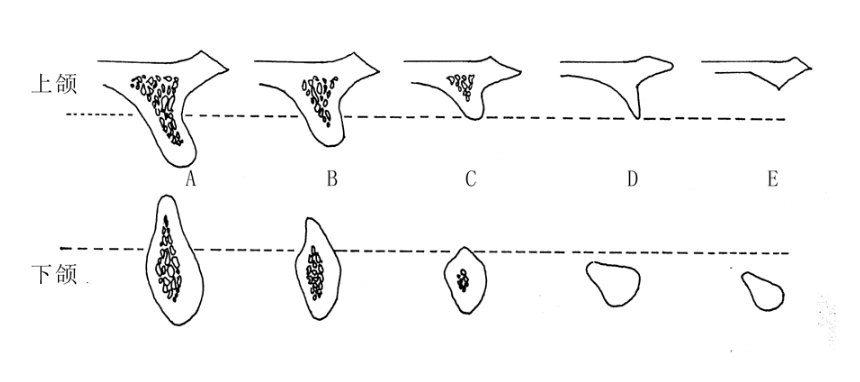

A:牙頜畸形是在兒童生長發育過程當中,由於遺傳、疾病、內分泌障礙以及營養不良、功能紊亂、口腔不良習慣、替牙障礙,還有其他因素的影響,導致牙頜面畸形,如牙齒排列不齊、上下牙弓咬合關係異常。頜骨大小形態位置異常、面部畸形等,稱為錯頜畸形,簡稱錯頜。……

A:牙頜畸形分因先天性遺傳因素造成和後天環境因素造成兩種,表現為頷骨、顱面錯位排列不齊形成畸形。建議可先去醫院口腔科拍取牙片,根據牙頜畸形情況制定治療方案,一般,常規的矯正方法有:傳統鋼絲矯正、陶瓷自鎖矯正、舌側隱形矯正和全透明隱形較正等,未成……

A:牙齒咬合不齊,主要有以下幾種方法治療:1、可以利用鑽針打磨牙齒的咬合面,恢復正常的咬合關係,這種只適用於輕度的咬合不良患者。2、重度的咬合不良患者,甚至牙頜畸形的患者,需要用正畸的手段來恢復牙齒的良好的咬合關係。正畸治療是目前治療錯頜畸形的……